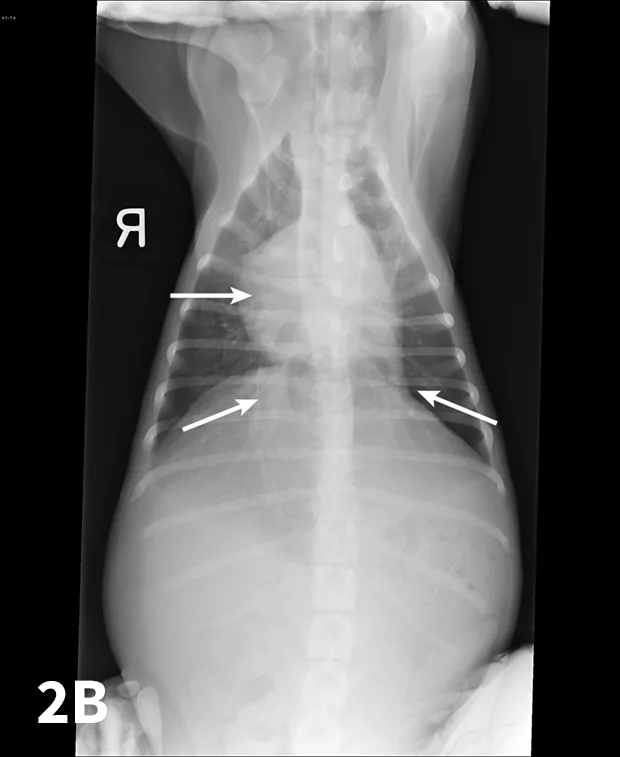

From the clinicians standpoint, echocardiography should be considered the most useful method to document PHTN (Figure 1).

Echocardiographic Doppler study documenting high tricuspid regurgitant velocity consistent with pulmonary hypertension. The modified Bernoulli equation [change in pressure = 4 (regurgitant velocity)2] may be used to estimate the systolic PAP. In the example shown, the tricuspid regurgitant velocity is 4.1 m/sec; thus, estimated PAP is 67 mm Hg.